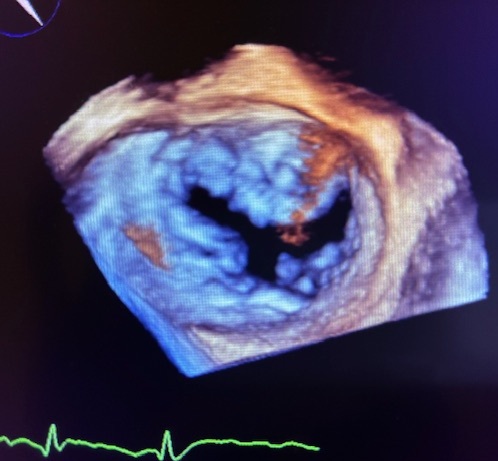

超音波検査は、どなたでも安心して繰り返し受けることができる検査です。甲状腺、乳腺、心臓、腹部、胎児、血管などを対象とし、臓器の形、大きさ、血液の流れ方を観察します。当検査室で最も行われている検査は、心臓超音波(心エコー)検査です。心エコー検査は、経胸壁心エコーと経食道心エコーがあり、経胸壁心エコーでは、胸にゼリーをぬり、探触子(プローブ)をあてることで、心臓の大きさ、壁の厚さ、弁(血液の流れを制御しています)の動き方を確認し、疾患の有無・重症度を診断します。不整脈、弁膜症、先天性心疾患等が対象となりますが、手術前後評価も行います。更に詳細な検査である経食道心エコーは、医師と共に行います。細い管を口から挿入し、2Dや3D画像で心臓内を観察し、手術の必要性等の判断が行われます。この検査では、苦痛を和らげるため、鎮静剤を使用して検査を行うことがあります。